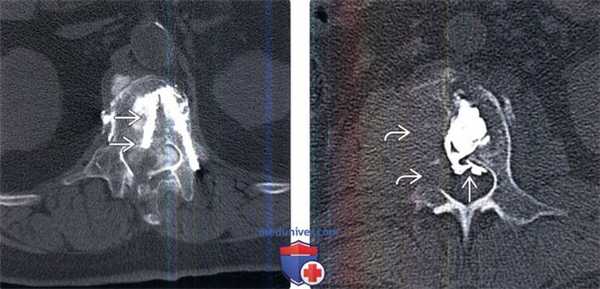

(Слева) На КТ-миелограмме в центральной части позвонка видна траектория введения цемента в ходе вертебропластики, которая могла быть получена только при трансдуральном введении иглы, т. е. значительно медиальней внутренней кортикальной стенки правого корня дуги.

(Справа) Аксиальный КТ-срез: признаки деструкции правой половины тела и корня дуги L2 позвонка остеолитическим метастазом опухоли. Предпринята попытка вертебропластики, в ходе которой произошла экстра ваза -ция цемента через дефект задней покровной пластинки в вентральный отдел эпидурального пространства.